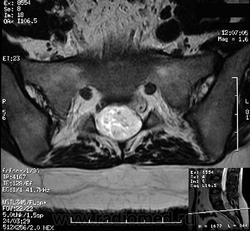

ГМ. СМ. Эпендимома миксопапиллярная. +

Эпендимома миксопапиллярная